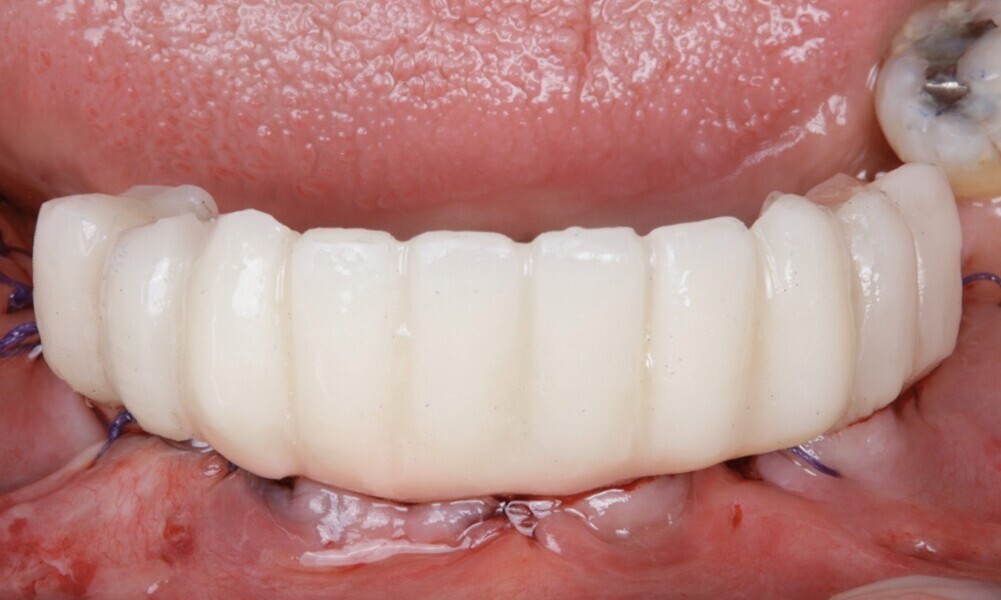

After a healing period of five months and successful osseointegration, the process for the definitive restorations was initiated. The chosen material was milled monolithic zirconia, and Variobase final abutments was used, placed on the screw-retained abutments to ensure excellent stability and retention of the definitive restorations (Figs. 69–75).

The soft tissue was in good condition, and the definitive restorations were placed (Figs. 76 & 77). After placing the definitive restorations, oral hygiene instructions were given to ensure proper care and prevent complications. Additionally, the occlusion was carefully checked and adjusted as needed (Figs. 78–83).